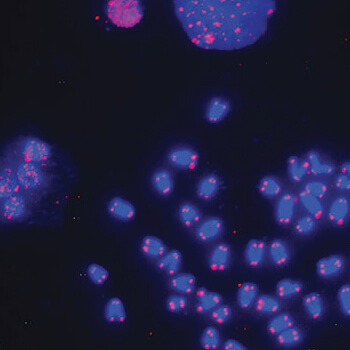

Gallery Exhibition: Art in Science

Pollak GalleryIntended to express and highlight the beauty of science – through images, drawings, and photos of natural forms and visualization of scientific, mathematic, and engineering processes based on the research and coursework of MU faculty and students. Images will reveal the elegance of science art in scientific results, observations, and failures.